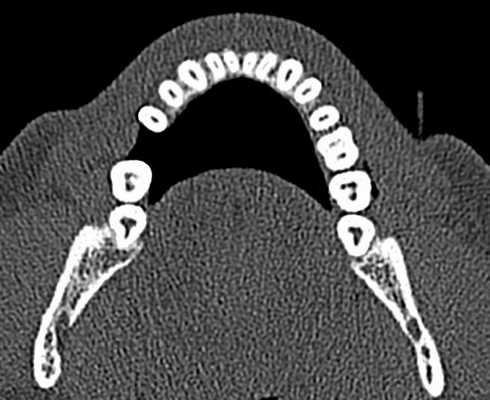

(Слева) На периапикальных рентгенограммах визуализируются четко очерченный рентгенонегативный тракт проводника зу6а (ПЗ) связанный с верхним краем коронки постоянного клыка нижней челюсти справа, мигрировавшего на противоположную сторону. Тракт доходит до альвеолярного гребня возле оставшегося временного клыка справа.

(Справа) На корональной (справа) и аксиальной (слева) КЛКТ визуализируется ПЗ, идущий от коронки импактного постоянного клыка нижней челюсти справа до альвеолярного гребня с язычной стороны от сохранного временного клыка.

2. Рентгенография проводника зуба:

• Интраоральная рентгенография:

о Четко отграниченный рентгенонегативный тракт, идущий от коронки импактного зуба до обычной области прорезывания в альвеолярном отростке

3. КТ проводника зуба:

• КЛКТ:

о Гиподенсный тракт с кортикальной пластинкой, идущий от зубного фолликула импактного зуба до альвеолярного отростка

(Слева) На кадрированной панорамной реформатированной КЛКТ визуализируется импактный третий моляр в области угла нижней челюсти. Четко визуализируется ПЗ, связанный с верхним краем фолликула. ПЗ рассматривается как тракт, по которому зуб проходит к обычному месту прорезывания в альвеолярном отростке. Обратите внимание на сдавление нижнечелюстного канала снизу.

(Справа) На профильном срезе КЛКТ у этого же пациента визуализируется проводник зуба.